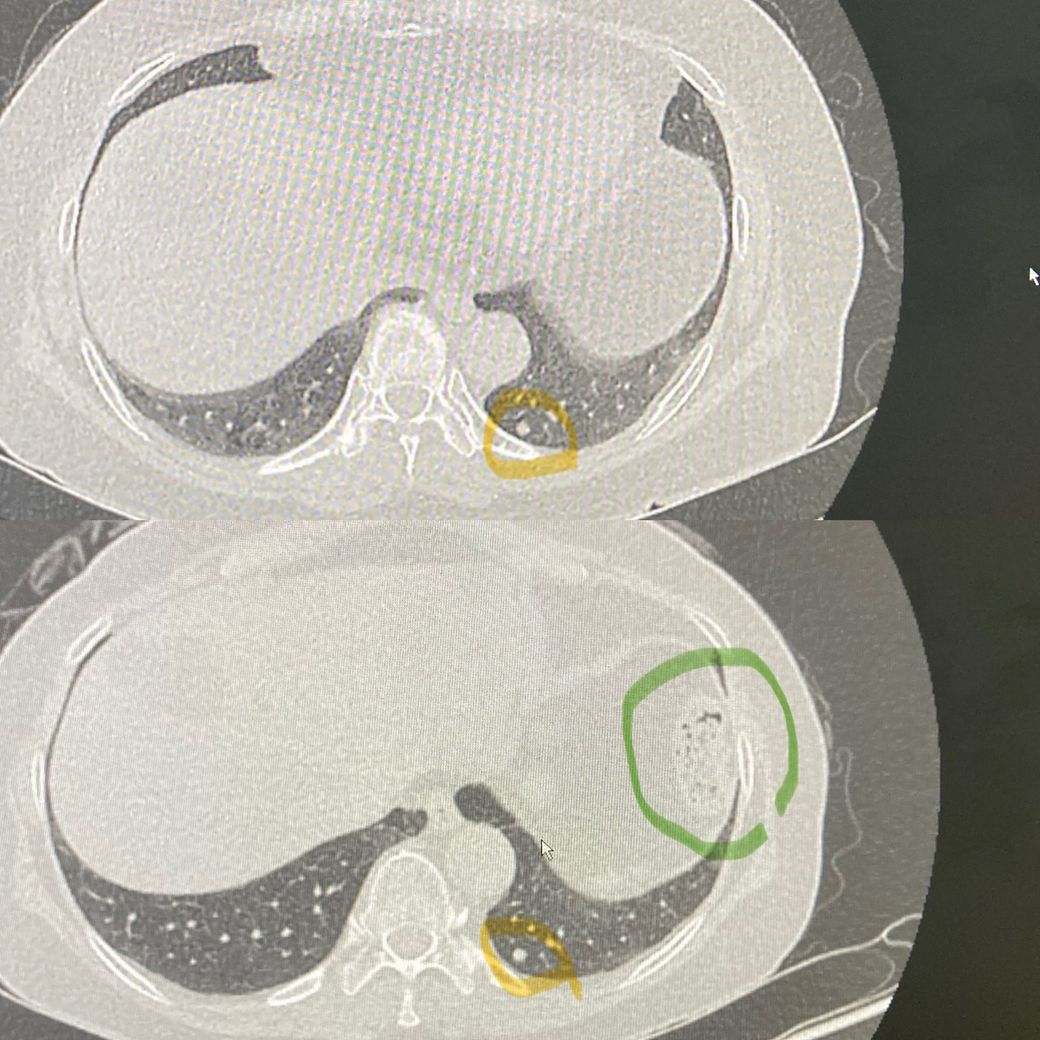

노란색 동그라미 폐 결절을 추적관찰 중인데

위에 사진이 3개월전 아래 사진이 최근에 찍은 사진입니다. 육안으로 봐서는 결절 크기는 변화가 없는것 처럼 보이는데.. 갑자기 초록색 동그라미 부분은 왜 저렇게 변한건가요? 벌집 처럼 생겼는데..... 무슨 문제가 생긴건가요?

저 장기가 뭘 찍은건지도 알려주시면 감사하겠습니다.

폐결절은 말씀하신대로 3개월 전 사진과 비교했을 때 큰 변화가 없어 보여서 추적관찰 하자는 말씀을 들으셨을 것 같습니다.

초록색으로 표시한 부분은 위 안에 있는 음식물로 보입니다.

노란색은 폐결절이 맞고 크기가 작으니 계속 추적관찰 하시면 되고,

초록색은 위장의 일부분이니 신경쓰지마세요 정상입니다.

동그라미 표시한 부분은 정상장기이며 대장의 일부분이

잘려 보이는 것으로 생각됩니다

폐결절은 크게 변화가 있어보이지는 않습니다

녹색으로 동그라미 친 부위는 위 속의 음식물이 관찰되는 것일 가능성이 매우 높아 보이는 소견입니다. 크게 걱정할 것 없어 보입니다.